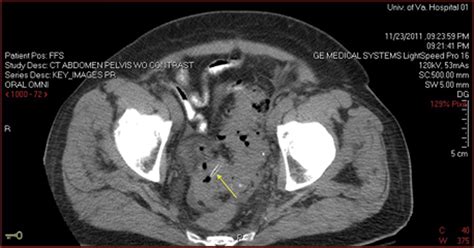

Diagnosing a colovesical fistula involves a combination of clinical evaluation, imaging studies, and sometimes endoscopic procedures. The diagnostic process typically includes:

• Imaging studies: CT scans, MRI, or barium enema can help visualize the fistula.